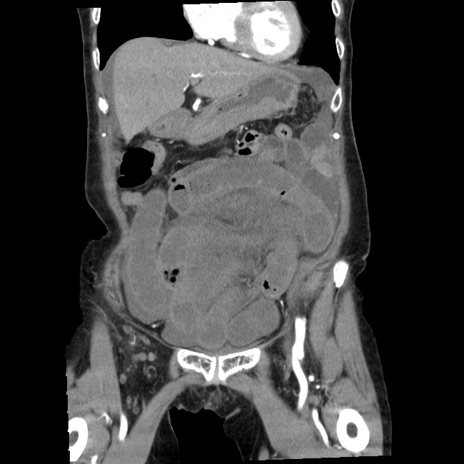

症例1(冠状断像)

【症例】80歳代女性

【主訴】腹痛

【現病歴】8時間前から腹痛あり来院。

【既往歴】糖尿病、脂質異常症、子宮体癌にて子宮全摘術

【身体所見】意識清明・会話良好だが腹痛で苦悶様、全腹部にわたって反跳痛と圧痛あり

【データ】WBC 13600、CRP 0.14、LDH 224、CK 90